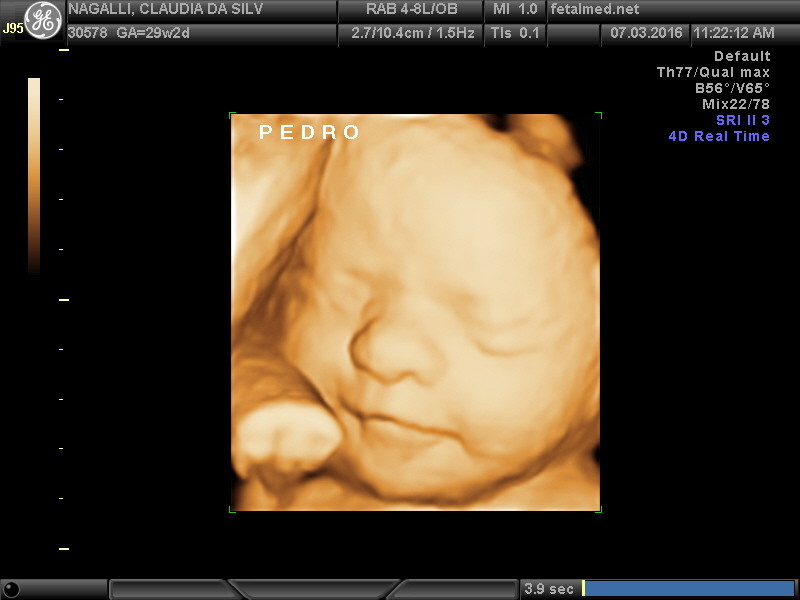

Seu bebê está crescendo e se desenvolvendo a uma velocidade incrível. As sobrancelhas e os cílios agora estão presentes e os cabelos estão mais espessos. As pálpebras se abrem e os olhos estão completamente formados. O corpo está mais rechonchudo. Pesa em torno de 1000-1300 gramas, mede cerca de 35 cm da cabeça aos pés. O tônus muscular está melhorando gradualmente. Os pulmões já são capazes de praticar a respiração mas se o bebê nasce agora ainda teria muita dificuldade para respirar. Tente falar bastante com ele pois já é capaz de reconhecer a sua voz.

Os bebês demonstram com freqüência movimentos de treinamento da respiração, contraindo e expandindo o diafragma, o que pode ser percebido ao ultrassom. Porém não existe troca gasosa a nível pulmonar, sendo que durante toda a gestação o oxigênio necessário para o bebê é proveniente da placenta.